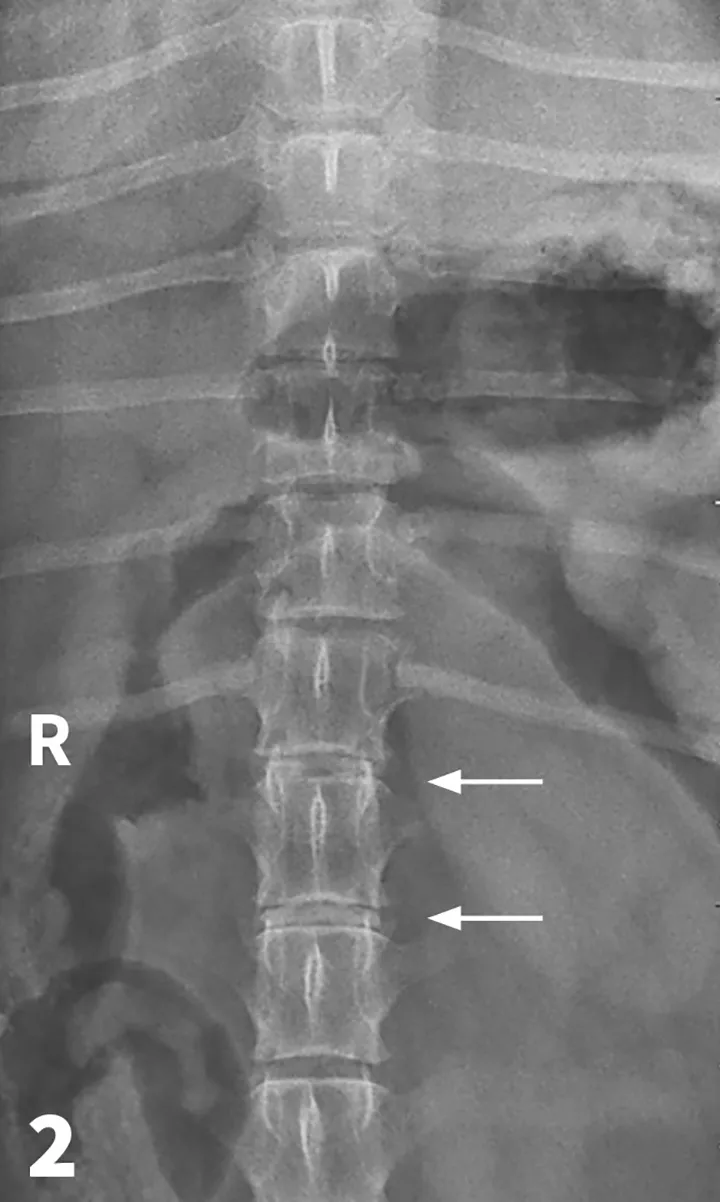

Figure 2

VD spinal radiograph. Mineralization and narrowing of the T13-L1 and L1-L2 disc spaces was noted (arrows).

The veterinarian administered 0.02 mg/kg acepromazine IM and 1 mg/kg morphine IM1 and obtained lateral and VD views of the TL vertebral column. (See Figures 1 & 2.) The radiographs showed no evidence of lytic change but did show mineralization and narrowing of the T13-L1 and L1-2 intervertebral disc spaces (arrows).